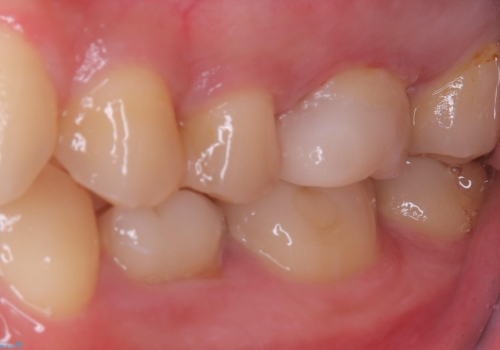

適合性、審美性、材料安定性からセラミックインレーでのやり替えとなりました。う蝕を除去いていくと、残存歯質が薄く破折リスクの高い部位が出てきたため患者さんにも説明し、アンレー窩洞としました。

セラミックアンレー接着時は、ラバーダム防湿を行っています。